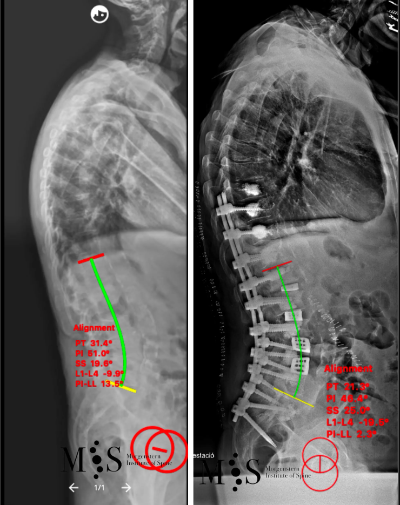

En aquests casos la cirurgia està indicada per corregir la deformitat i sobre tot per alleujar el dolor causat per l’escoliosi degenerativa. En els casos més severs d’escoliosi fins i tot pot ser necessari realitzar una osteotomía (tallar parcialment una vèrtebra) per poder redreçar la columna vertebral deformada del pacient.

Al Morgenstern Institute of Spine, utilitzem tècniques quirúrgiques endoscòpiques i percutànies per corregir les escoliosis degeneratives i permetre que el pacient es recuperi el més aviat possible. L’alta hospitalària es sol donar als pocs dies de la cirurgia.